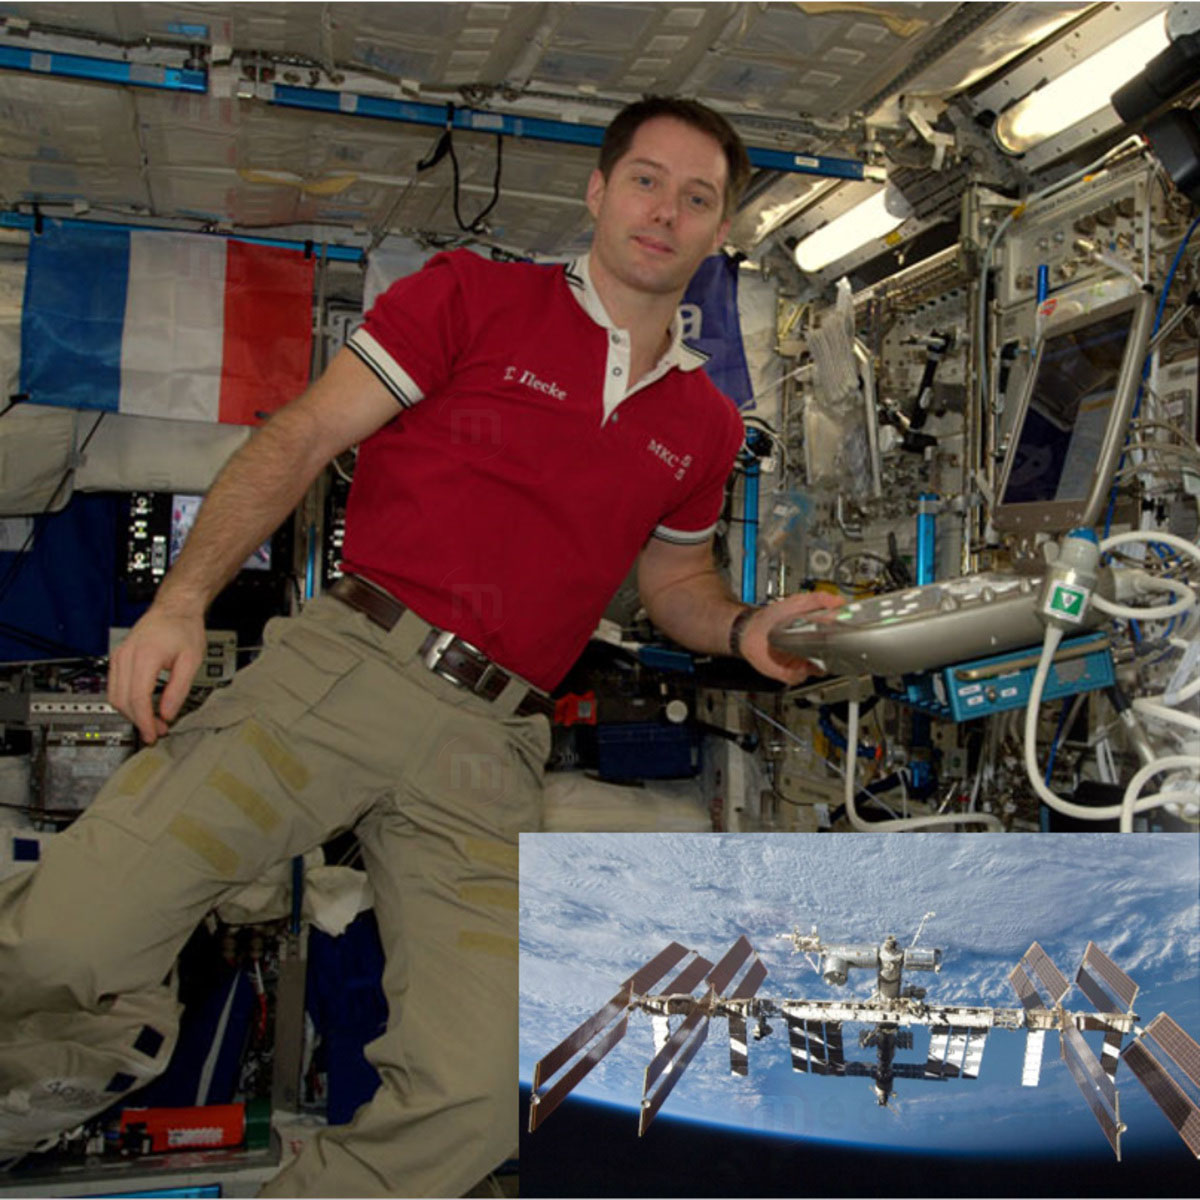

Echographe HD Sonoscanner Orcheo Lite

Orcheo Lite, c’est la polyvalence et la performance où que vous soyez.

Bénéficiant des modes d’imagerie les plus avancées (THI, Compound Imaging, Power and Directional Power…), l’Orcheo Lite est la réponse à vos exigences les plus pointues sur de multiples applications cliniques.

Son interface conviviale et simple d’utilisation fait accéder l’imagerie à ultrason à un nouveau degré de productivité en vous permettant de réaliser des examens plus rapides et plus sûrs.

- Poids : 5.5kg

- Dimensions : 42cm X 37cm X 8.5cm

- Batterie rechargeable. Autonomie : 1h30 en fonctionnement

- Chariot dédié ultra maniable pour une plus grande mobilité